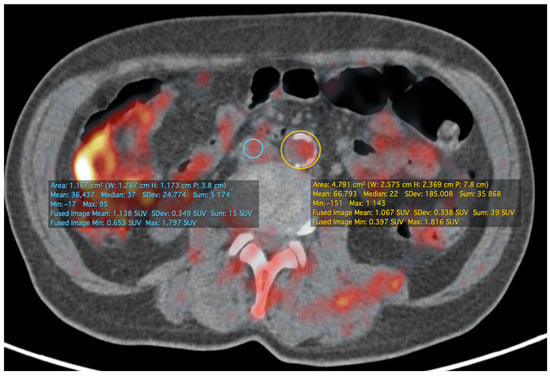

- Koa, B.; Borja, A.J.; Yellanki, D.; Rojulpote, C.; Tran, J.; Zhang, V.; Werner, T.J.; Alavi, A.; Revheim, M.-E. 18F-FDG-PET/CT in the assessment of atherosclerosis in lung cancer. Am. J. Nucl. Med. Mol. Imaging 2021, 11, 1–9. [Google Scholar]

- Rominger, A.; Saam, T.; Wolpers, S.; Cyran, C.C.; Schmidt, M.; Foerster, S.; Nikolaou, K.; Reiser, M.F.; Bartenstein, P.; Hacker, M. 18F-FDG PET/CT Identifies Patients at Risk for Future Vascular Events in an Otherwise Asymptomatic Cohort with Neoplastic Disease. J. Nucl. Med. 2009, 50, 1611–1620. [Google Scholar] [CrossRef] [PubMed]

- Mehta, N.N.; Torigian, E.A.; Gelfand, J.M.; Saboury, B.; Alavi, A. Quantification of Atherosclerotic Plaque Activity and Vascular Inflammation using [18-F] Fluorodeoxyglucose Positron Emission Tomography/Computed Tomography (FDG-PET/CT). J. Vis. Exp. 2012, e3777. [Google Scholar] [CrossRef] [PubMed]